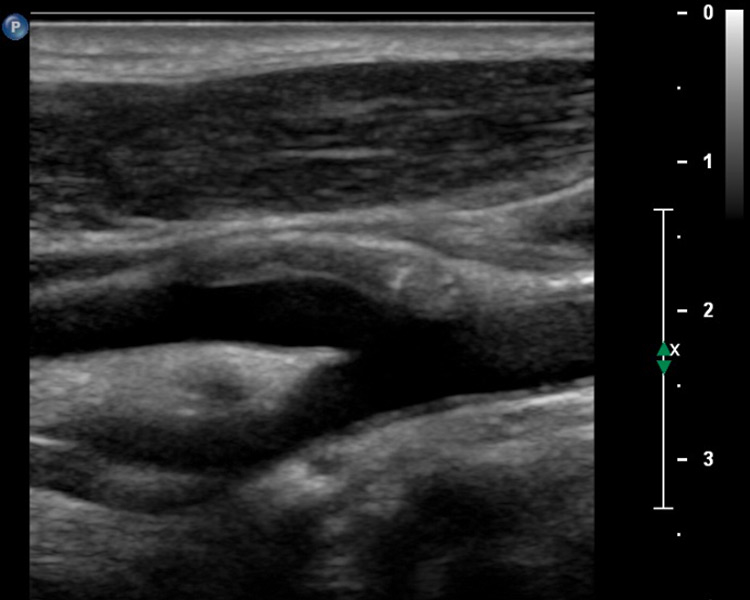

Figure 1

A 58-year-old patient with myocardial infarction 2 months previously with hypoechogenic plaque at the origin of the left internal carotid artery on B-mode ultrasound (A). Extensive intraplaque neovascularisation (arrows) on CEUS imaging (B).

Figure 2

A 61-year-old patient with asymptomatic high-grade stenosis at the origin of the left internal carotid artery on colour Doppler ultrasound (A). Moderate intraplaque neovascularisation within the carotid stenosis at the near wall on CEUS imaging (arrows) and no neovascularisation at the far wall (B).

In our own clinical study, we analysed 293 atherosclerotic lesions with standard and CEUS imaging [29]. The degree of intraplaque neovascularisation was graded visually as no, moderate or extensive enhancement. Similar to other investigators we found that predominantly hypoechoic carotid plaques on B-mode ultrasound, known to be associated with an increased risk of cardiovascular events significantly more often, had a higher grade of intraplaque neovascularisation on CEUS (fig. 1). In accordance with the concept that more vulnerable atherosclerotic lesions had a higher degree of neovascularisation, we found also that intraplaque neovascularisation on CEUS correlated well with lesion severity based on the degree of stenosis and plaque thickness (fig. 2).